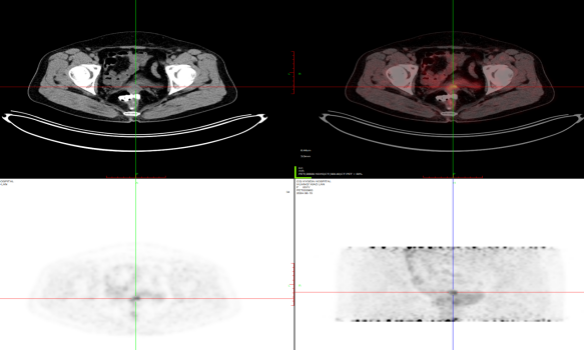

宫颈癌术后复发

乙状结肠癌术后复发